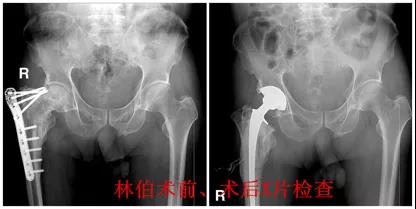

近日,佛山市第二人民医院骨科为一名髋部骨折术后内固定失效患者成功实施了髋关节翻修手术。

82岁的林伯,4年前因髋部骨折在当地医院做了手术,后面出现内固定物失效,下肢短缩、跛行、疼痛难忍,作为退伍军人的他难以接受不能独立行走的痛苦,从湛江辗转到广州各大省级医院,都因为手术难度和患者高龄等原因,建议林伯保守治疗。不甘余生坐在轮椅度日的林伯,怀着希望来到市二医院骨科门诊就诊,骨科主任邱华耀为他详细评估病情。邱华耀主任认为:患者为股骨粗隆间骨折术后,骨折端畸形愈合,伴有股骨头缺血性坏死;患侧肢体长度明显短缩,原内固定已经失效并影响髋关节活动。为恢复患者步行,提高生活质量,髋关节翻修术是唯一有效的治疗手段。

术前准备均已完善后,骨科中心主任邱华耀带领手术团队,为林伯实施手术。术中手术医生、麻醉师及器械、巡回护士配合默契,手术顺利完成。术后第二天,林伯便能扶着助行器下地行走锻炼。至术后第7天,林伯康复进展良好,按计划办理出院。临行前,林伯一家郑重地向骨科团队递上一面锦旗表示感谢!